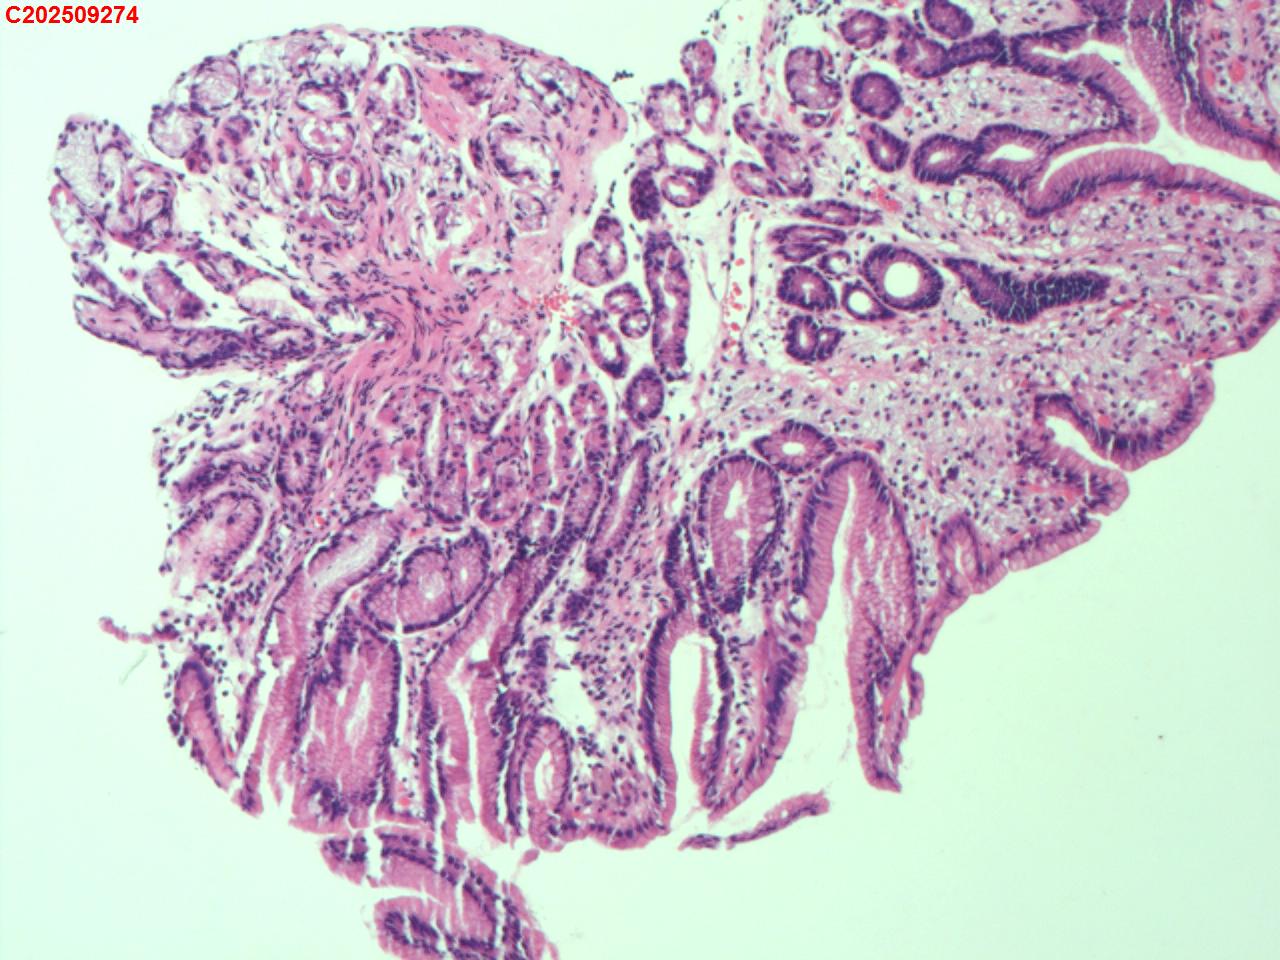

胃窦粘膜

性别

女

年龄

60岁

临床诊断

胃黄斑瘤

一般病史

体检

标本名称

大体所见

胃窦大弯偏前壁可见一扁平状淡黄色粘膜隆起。

图1

送检粘膜呈轻度慢性炎伴表浅糜烂伴胃黄斑瘤形成